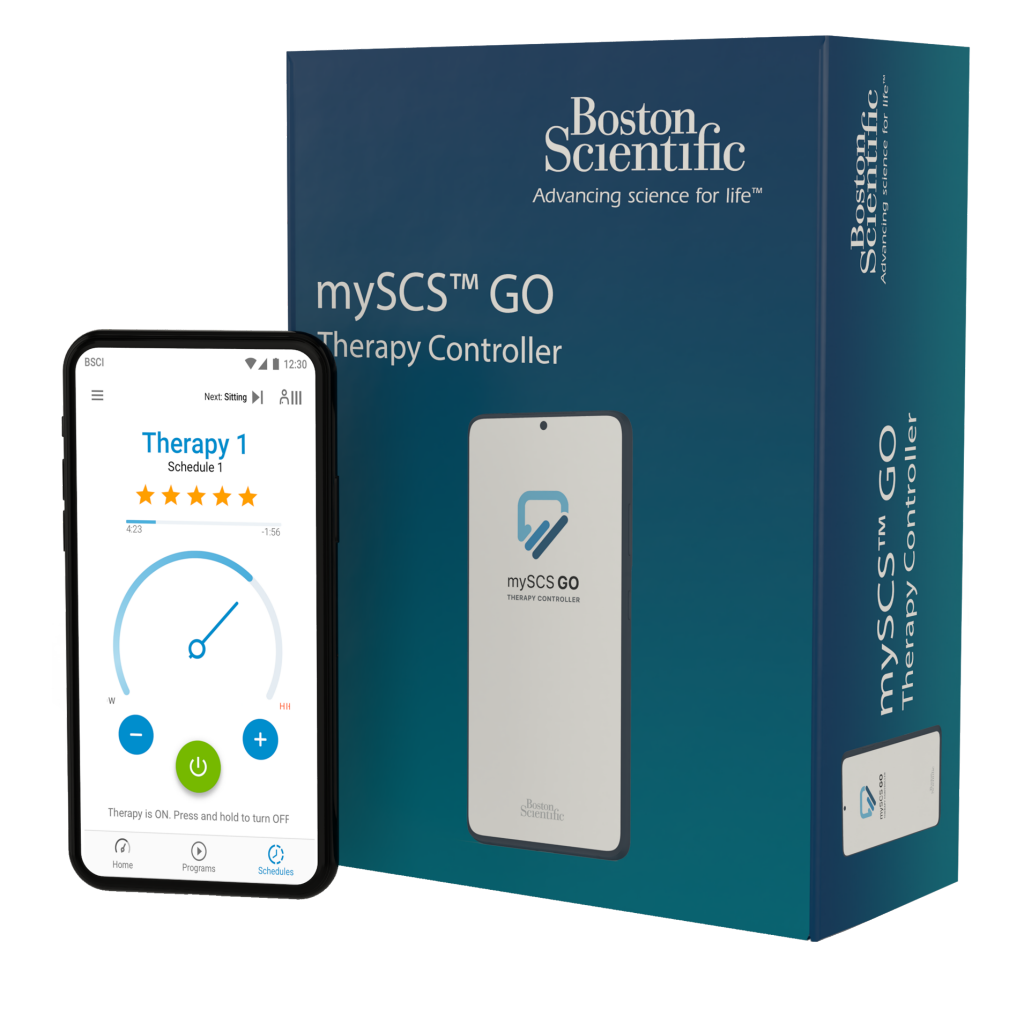

Therapeutic Exercise for Lumbopelvic Stabilization: A Motor。Neuroscience Chapter 13: Spinal Region Flashcards | Quizlet。Correction of Thoracic Hypokyphosis in Adolescent Scoliosis。Amazonで購入した未使用の極美品です。Spinal Cord Stimulation (SCS) For Chronic Pain | Pain.com。自分で取り寄せすると洋書なので輸入に数週間かかると思うので、到着までかなりの日数がかかってしまいます。医学生・研修医のための神経内科学。本商品は東京からの発送なので数日で到着するため、その点良いかと思います。超音波専門医認定試験問題集 第7版。よろしくお願いします。歯科衛生士臨床のすべて。